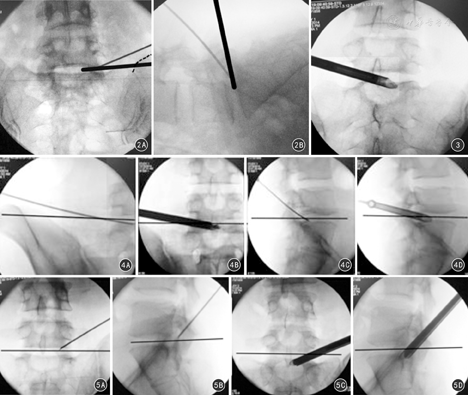

按照Ferguson位透视方法,正位相目标间隙的椎体下缘终板和椎体上缘终板要呈一条直线。侧位相X线透视的中心线与椎体后缘的水平线重叠,使目标间隙双侧的椎间孔重叠在一起。穿刺进针点在X线透视正位上位于术侧上下椎弓根内侧缘的连线上,透视侧位上位于上下椎体后缘连线上(图1)。在训练有素的放射技师配合下,本组手术中每例患者最少需透视2次,一次为穿刺定位像、一次为穿刺至小关节外侧像,最多10次,平均为6次。

根据YESS技术由内向外的理念,我们改良穿刺角度,降低穿刺针与冠状面的夹角,见图2,图3,图4,图5。在CT或MRI水平扫描的影像学上确定穿刺的角度后,根据影像学的标尺测量棘突距离皮肤进针点的距离,然后进行实际操作。穿刺首先触碰的是小关节侧面,随后逐渐增大穿刺角度,穿刺有落空感后进行透视,此时穿刺针已进入椎小关节前缘的靶点。引导工作导管在不磨除骨质条件下,可直接使工作面到达硬膜囊和椎体后缘之间的后纵韧带。建立好工作通道后,使工作面直接面对后纵韧带边缘,从而更加有利于观察椎管内容物、后纵韧带及椎间盘组织三层结构,见图6,图7。